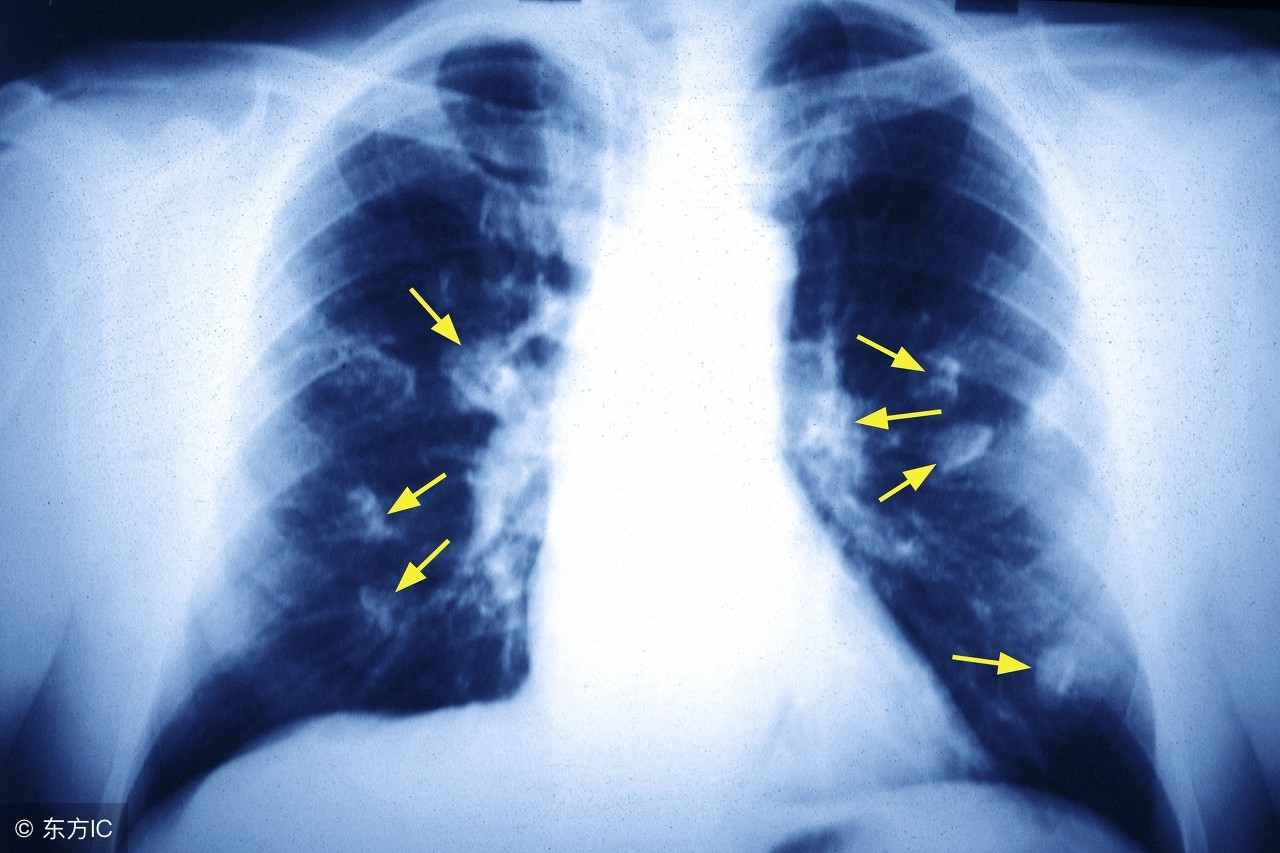

随着社会的发展,人们生活水平的在不断的提升,但是通过调查得出患有肺癌的人数也在不断的增加,肺癌让患者受到了很严重的痛苦,相信大家都想知道,究竟肺癌更倾向于哪类人呢?

肺癌高危人群就是指肺癌发病率高、肺癌相对危险度高的一部分人。